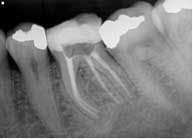

The patient was given treatment options and informed consent, and elected to begin treatment immediately. Profound anesthesia was achieved using two carpules of 2% lidocaine for IANB and one carpule of Septocaine for long buccal infiltration. The tooth was isolated with a rubber dam and accessed under Global operating microscope using round burs and an Endo-Z bur. The distal canal was located in its typical orientation, centered buccolingually between the mesial canals. However, the canal leading to the radix entomolaris was found far to the lingual and off-center. Working length was determined using Root ZX II electronic apex locator. ISO size 6, 8, and 10 files were used to create initial glide path. Instrumentation was completed using ProGlider files to establish glide path, and a combination between Protaper and Vortex Blue files with full-strength sodium hypochlorite irrigation. QMix was placed into the canals after irrigation and agitated with EndoActivator to remove the smear layer and for its antibacterial properties. The canals were filled using warm vertical condensation with System B and Calamus backfill. The patient was given a six-month follow-up appointment and ibuprofen 600 mg for postoperative discomfort.